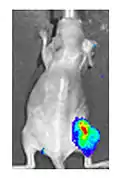

Both in the laboratory and in the clinic it is useful to have a simple means of identifying cells infected by the experimental virus. This can be done by equipping the virus with "reporter genes" not normally present in viral genomes, which encode easily identifiable protein markers. One example of such proteins is GFP (green fluorescent protein) which, when present in infected cells, will cause a fluorescent green light to be emitted when stimulated by blue light.[87][88] An advantage of this method is that it can be used on live cells and in patients with superficial infected lesions, it enables rapid non-invasive confirmation of viral infection.[89] Another example of a visual marker useful in living cells is luciferase, an enzyme from the firefly which in the presence of luciferin, emits light detectable by specialized cameras.[87]

Radioiodine

Addition of the sodium-iodide symporter (NIS) gene to the viral genome causes infected tumour cells to express NIS and accumulate iodine. When combined with radioiodine therapy it allows local radiotherapy of the tumour, as used to treat thyroid cancer. The radioiodine can also be used to visualise viral replication within the body by the use of a gamma camera.[87] This approach has been used successfully preclinically with adenovirus, measles virus and vaccinia virus.[94][95][96]

- 1 2 3 Haddad D, Chen CH, Carlin S, Silberhumer G, Chen NG, Zhang Q, Longo V, Carpenter SG, Mittra A, Carson J, Au J, Gonen M, Zanzonico PB, Szalay AA, Fong Y (2012). Gelovani JG (ed.). "Imaging characteristics, tissue distribution, and spread of a novel oncolytic vaccinia virus carrying the human sodium iodide symporter". PLOS ONE. 7 (8): e41647. Bibcode:2012PLoSO...741647H. doi:10.1371/journal.pone.0041647. PMC 3422353. PMID 22912675.